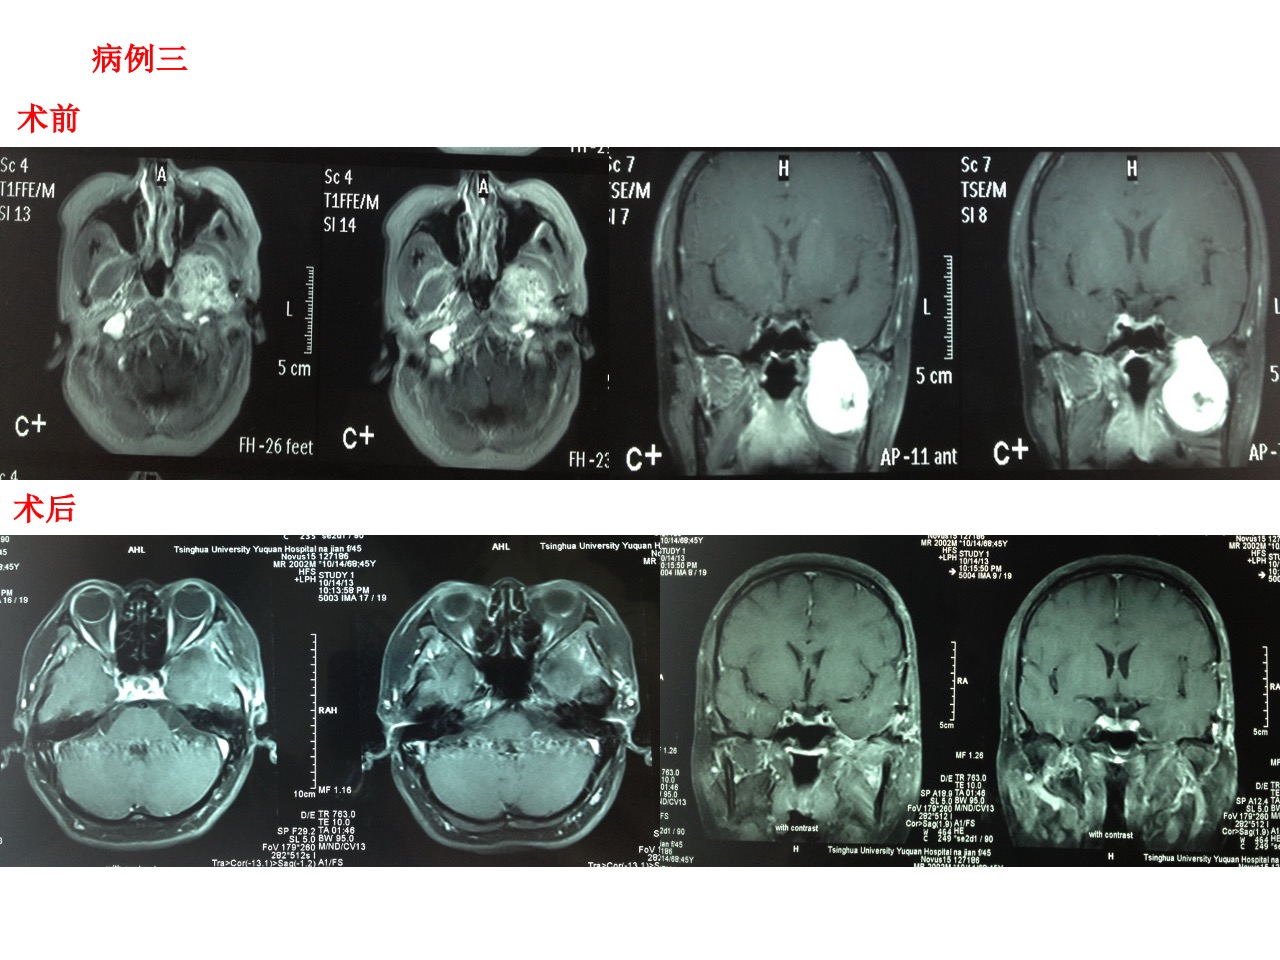

病例3,女性,45岁。主因头痛左侧面部麻木、脸部消瘦2个月入院。查体:左侧面部痛温觉减退,左侧咬肌轻度萎缩。CT提示中颅窝底骨质吸收破坏。MRI示中颅窝底鞍旁长T1长T2占位,可明显强化。无脑膜尾征。肿瘤主体部分(3/4)突入颞下窝。术后强化MRI提示肿瘤切除理想。